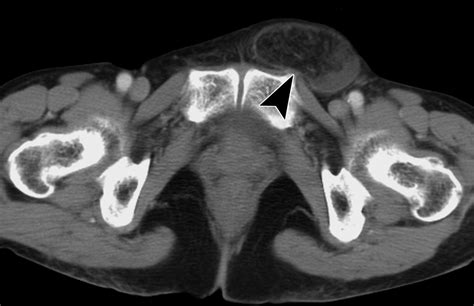

A physical examination is the gold standard for diagnosing these conditions. A doctor will typically perform a “cough test” while palpating the groin area to feel for an impulse or bulge. Because the indirect hernia vs direct distinction is based on where the pressure is felt against the doctor’s fingers, the examination can often help distinguish between the two.

In some cases, imaging studies like an ultrasound or MRI may be ordered to confirm the diagnosis, especially if the physical exam is inconclusive or if the hernia is small. Accurate diagnosis is vital because an indirect hernia is more likely to extend into the scrotum, whereas a direct hernia typically remains localized to the groin.